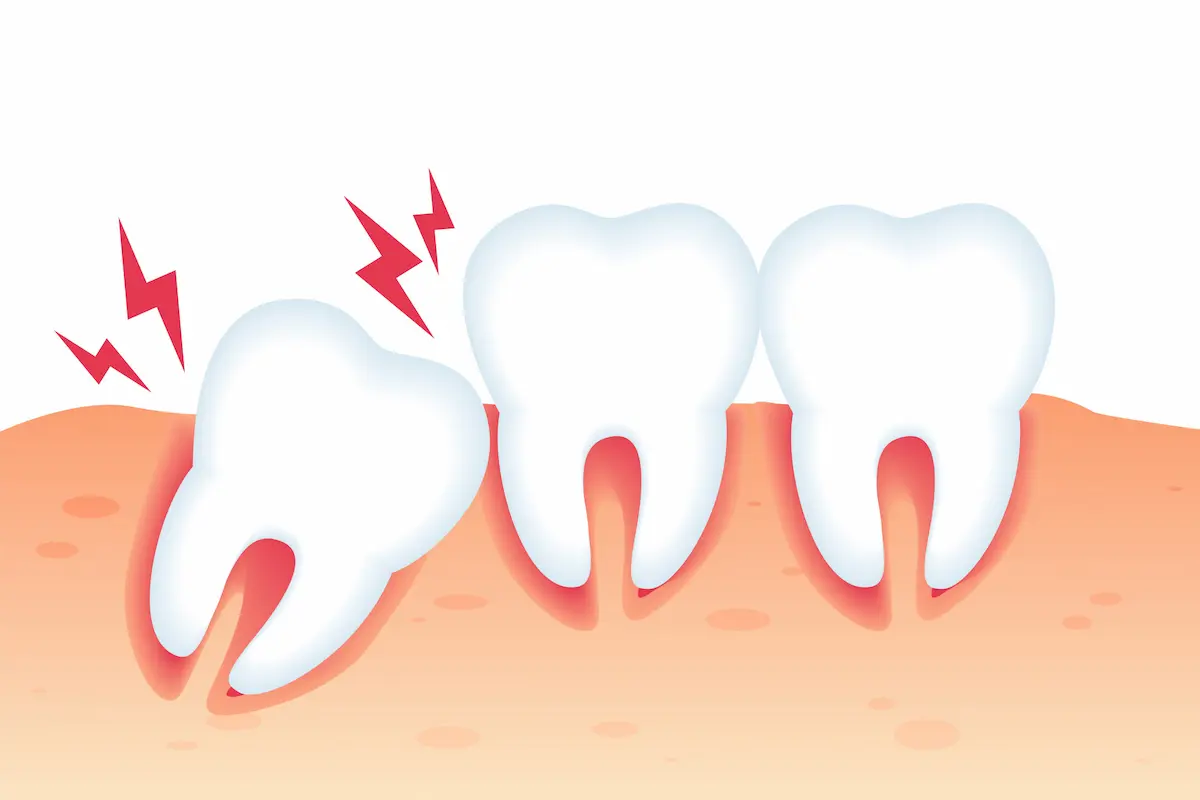

جلوگیری از آسیب به دندان های دیگر: اگر دندان عقل به طور نامناسب در فک قرار گیرد، ممکن است به دندان های دیگر آسیب برساند. به عنوان مثال، دندان عقل ممکن است دندان های مجاور را کج کند و یا به لثه ها و استخوان فک آسیب برساند. کشیدن دندان عقل می تواند از بروز این آسیب ها جلوگیری کند.

دندان عقل نهفته با زاویه به سمت دندان جلویی: این دندان به سمت دندان جلویی خود رشد میکند و میتواند باعث کج شدن یا فشار آوردن به این دندان شود.